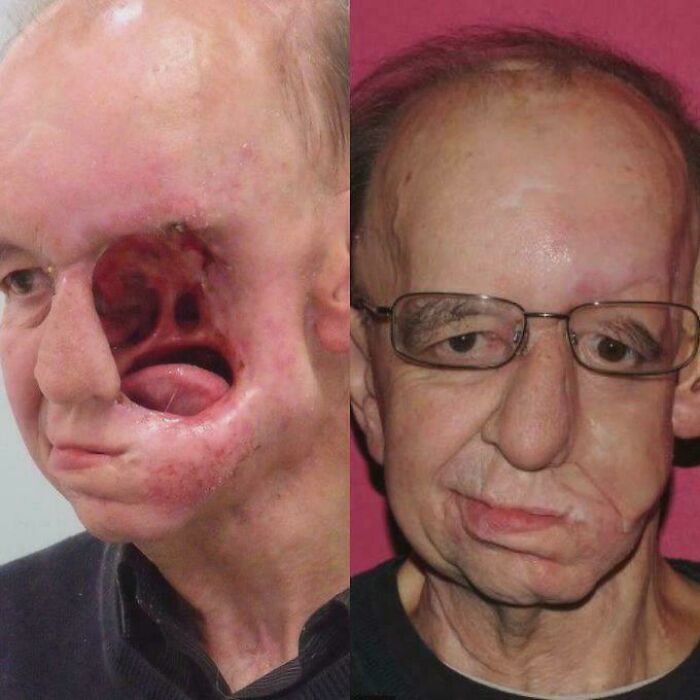

3D Printed Face

"Eric Moger, at 62 years old had recently gotten engaged and was satisfied with where his life was going. Little did he know, life would take an unexpected turn with one trip to the doctor.

While undergoing surgery to remove nasal polyps the doctors had found a tumor the size of a tennis ball, in the left side of his face. Upon waking up, Moger would soon learn his fate.

Shortly after the first surgery, Moger would undergo the second surgery that would remove his tumor and ultimately most of the left side of his face.

During recovery he experienced depression and loss of self-esteem. He would attempt multiple surgeries to fix the gaping hole, although nothing would work. He began to lose hope.

That is until 3D printing technology was brought to his attention. Another surgeon would 3D print a prosthetic mask and a mouth implant that would allow him to speak and eat, without issue. Moger now is happily married and cancer free."